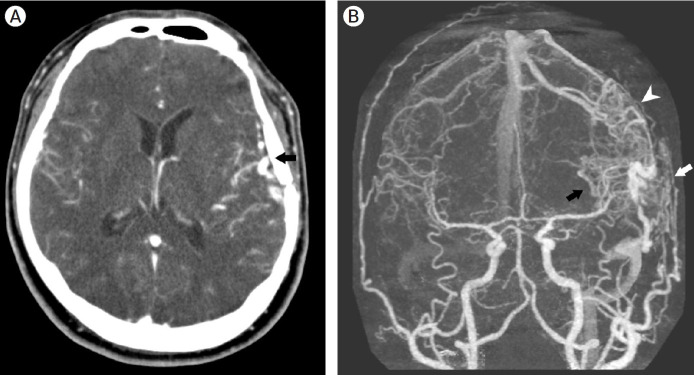

Craniotomy is known as a cause of iatrogenic dural cerebral arteriovenous fistula (AVF). However, mixed pial and dural AVFs after craniotomy are extremely rare and require accurate diagnosis and prompt treatment due to their aggressiveness. We present a case of an iatrogenic mixed pial and dural AVF diagnosed 2 years after pterional craniotomy for surgical clipping of a ruptured anterior choroidal aneurysm. The lesion was successfully treated using single endovascular procedure of transvenous coil embolization through the engorged vein of Labbe and the superficial middle cerebral vein. The possibility of the AVF formation after the pterional approach should always be kept in mind because it usually occurs at the middle cranial fossa, which frequently has an aggressive nature owing to direct cortical venous or leptomeningeal drainage patterns. This complication is believed to be caused by angiogenetic conditions due to coagulation, retraction, and microinjuries of the perisylvian vessels, and can be prevented by performing careful sylvian dissection according to patient-specific perisylvian venous anatomy.